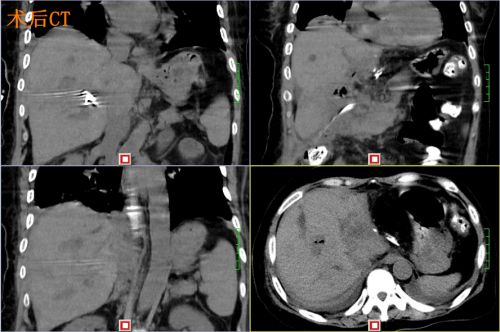

术后ct

尹女士肝内胆管多发结石,结石遍布肝脏所有胆管,要将结石全部清除,手术难度很大。首席专家吴金术教授和肝胆医院院长蒋波教授的指导下,2月20日,尹新民教授团队为尹女士实施腹腔镜下胆囊切除、胆总管切开取石、左肝管劈开取石、S5胆管劈开取石、右肝后叶及尾叶取石、S8胆管钬激光碎石、肝方叶切除、左肝外叶切除、肝门胆管整形、胆总管离断一胆肠内引流术。

患者肝内布满结石,又有胆道畸形和狭窄,手术实施非常困难。为了把结石清除干净,尹新民教授团队遵循吴金术教授20字肝胆管结石治疗方针——“取尽结石,解除狭窄,切除病肝,矫正畸形,通畅引流”,用尽十八般武器,坚持不懈,奋战14个小时,最终把结石清除干净,术中出血不足200毫升。